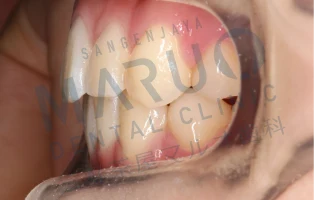

治療前

上の前歯が前に出ていることと歯のでこぼこを治したいとのことでした。

治療中

表側に装置をつける矯正を選択されました。上下左右の大人の歯を1本ずつ抜いて歯を並べ、前歯を後方に動かすスペースを確保しました。

動的治療終了時

動的治療期間は約2年6ヶ月でした。上の前歯の傾斜は改善し、歯のでこぼこは解消され、患者様に満足いただける結果となりました。

| 主訴 | 上の前歯が前に出ている 歯のでこぼこ |

|---|---|

| 診断名 | 上顎前突 叢生 |

| 年齢 | 13歳 |

| 治療に用いた主な装置 | マルチブラケット装置 |

| 抜歯部位 | 上下両側第一小臼歯 |

| 治療期間 | 2年6ヶ月 |

| リスク、副作用 | むし歯や歯周病、歯根吸収、治療後の後戻りの可能性があります |